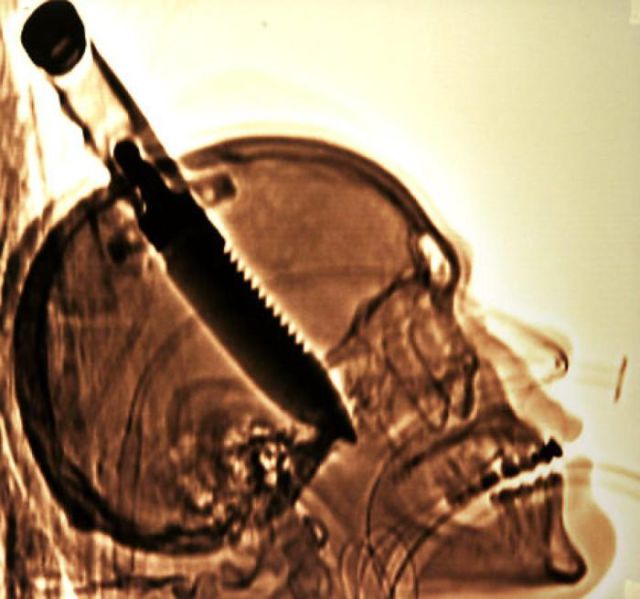

These x-rays will make you wonder how this could ever have happened in the first place.